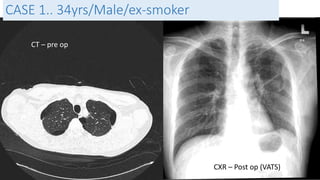

CASE 5

• 34 yrs / Indonesian / Female

• G4 P2 L1 [21 weeks pregnant]

• BGHx:

• PDA under cardio follow up detected

2006 during 3rd pregnancy

• ECHO: PDA 0.47cm, Left to Right shunt,

No evidence of Pulm. HTN

• Detected to have ? Lung disease in

2008 not worked up.

• Presented with Shortness of breath

for 10/7 and cough x 3/7

• O/E

• Mildy tachpneoic, RR 24/min

• Speaking in full sentences

• Pulse: 88/min

• BP: 130/70 mmHg

• sPO2: 97% Room air

• Lungs: Reduced air entry on

the right side with

hyperresonant on right side

BASELINE - 2008 On presentation

CASE 5. 34yrs/Indonesian

• Diagnosis

• Secondary spontaneous pneumothorax

• Community Acquired Pneumonia

• To work up for underlying Chronic Lung

Disease – TRO TB